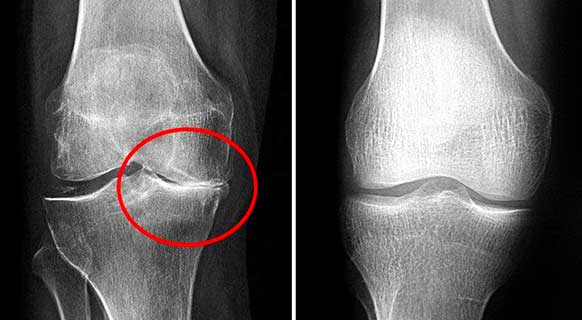

นี่คือภาพรังสีเอกซ์ของข้อเข่าที่ถูกทำลาย

ปัญหาคือ คนส่วนใหญ่มักไม่สนใจอาการแรกเริ่ม พวกเขาคิดว่าอาการปวดเกิดจากความเหนื่อยล้าหรืออายุที่มากขึ้น แต่เมื่ออาการรุนแรงจนทนไม่ไหว โรคก็ลุกลามไปมากแล้ว และการรักษาก็ต้องใช้เวลานานและความพยายามมากขึ้น